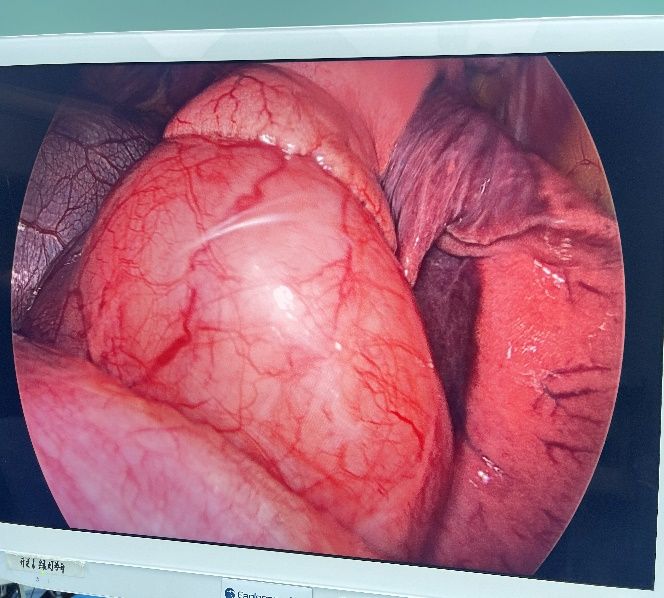

在2024年10月21日,姜建涛主任医师、李建忠副主任、赵丹文医师为小张实施了手术治疗,术中先尝试胸腔镜手术,腔镜下可见食管下段至贲门巨大隆起性病变,姜主任评估后认为腔镜下操作困难大,遂将操作孔延长至5cm行手术,术中发现肿瘤环食管周生长,完整剥除及其困难,但考虑小张年轻,未避免切除食管而对小张以后的生活造成影响,姜主任团队仔细操作,尽可能为小张保住食管,在姜主任及其团队的精心操作下,手术顺利,手术仅历时一个多小时,便将肿瘤完整剥除,剥除下来的肿瘤长径达到了快13cm,试水检查食管粘膜未损伤。在术后第一天查房的时候小张已经能下地活动了,激动的拉着姜主任的手,感谢姜主任为她成功实施手术并保住了食管,感叹姜主任的高超技艺,现小张一切恢复顺利,已康复出院。